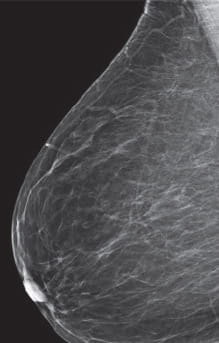

Radiologists classify breast density using a four-level density scale, as determined by a mammogram:

- Category A: Almost entirely fatty

- Category B: Scattered areas of fibroglandular density

- Category C: Heterogeneously dense

- Category D: Extremely dense